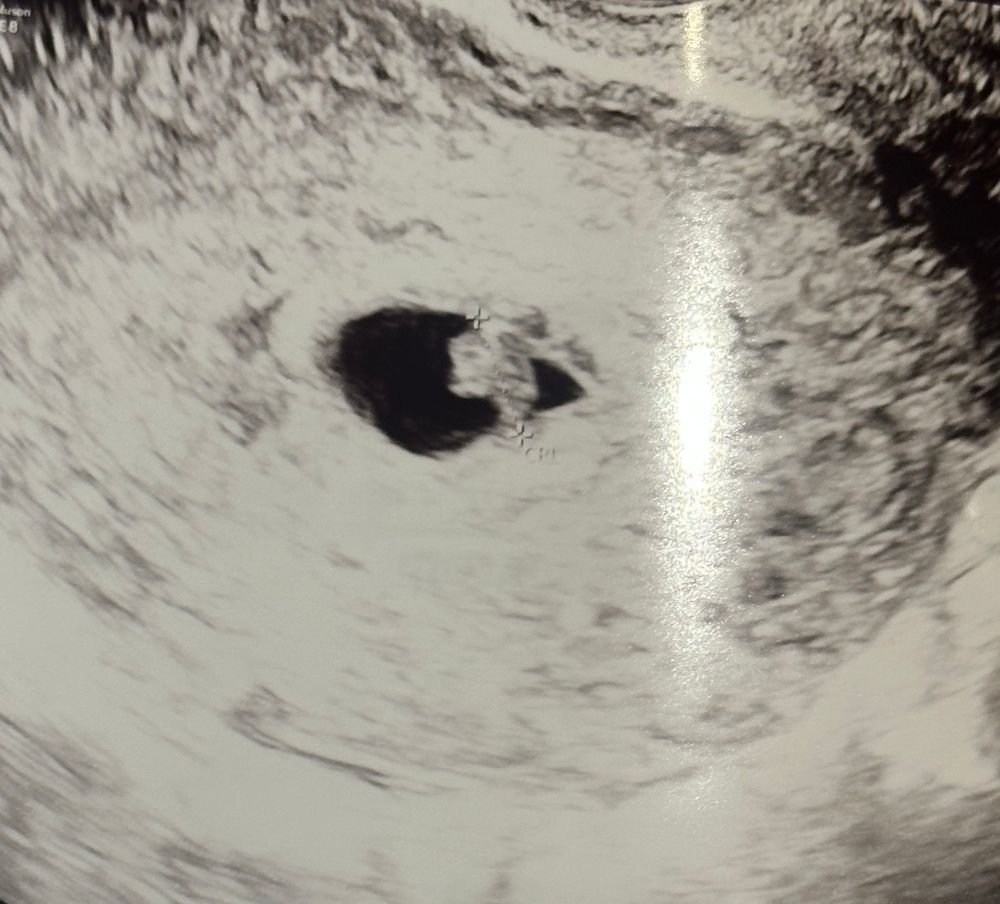

УЗИ 6+5 недель

Девочки, я живу за границей, пошла сегодня на УЗИ, срок 6 недель 5 дней, начиталась форум про сердцебиением и параметры, сколько должно быть… узистка сказала сердцебиение есть, а на вопрос сколько-ответила-мы не меряем, это неважно сейчас🙈 параметры, которые указаны в результатах только CRL (КТР) 8,2 и сердцебиение-прослушивается….ровно неделю назад было КТР-2 мм, сердцебиение-не прослушивается…..и как теперь быть уверенной, что все хорошо…Мой внутренний крнтролер хочет знать цифры сердцебиения😂🙈 или это действительно неважно на этом сроке?